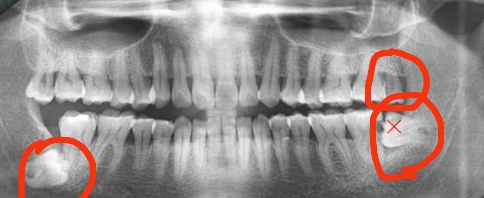

①智慧齒威脅鄰牙:當智慧齒威脅到鄰牙的時候,智慧齒阻生或者生長空間有限,此時應該考慮拔除智慧齒。否則長此以往,鄰牙可能被擠歪頂壞,出現一系列後遺症。因此此時智慧齒應該考慮拔除。

②智慧齒導致炎症複發:智慧齒導致炎症反複複發,此時難以根除,可以考慮拔除。

③智慧齒導致食物填塞:如果智慧齒導致鄰牙食物填塞,極其容易導致鄰牙側面蛀牙,並且蛀牙情況難於杜絕,此時考慮拔除。

④智慧齒埋伏生長:當智慧齒完全不能生長出來,此時可以考慮拔除。